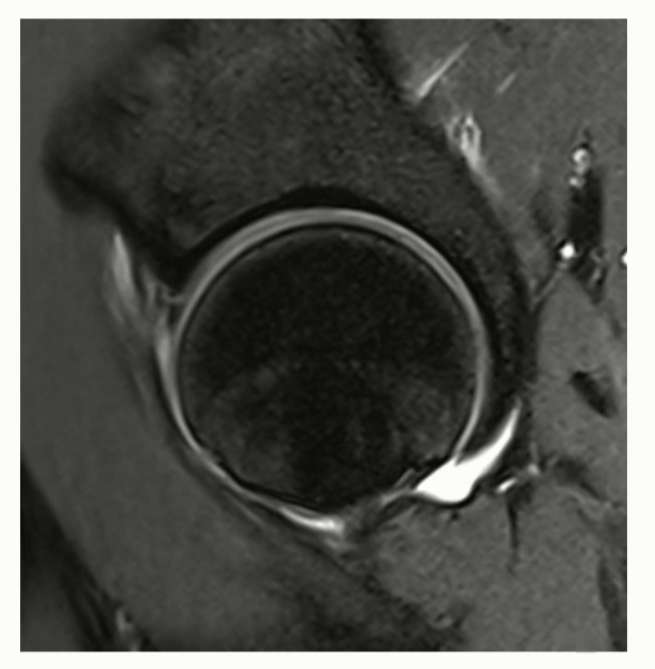

Case 1)

antero-superior labrum에 발생한 detachment 소견